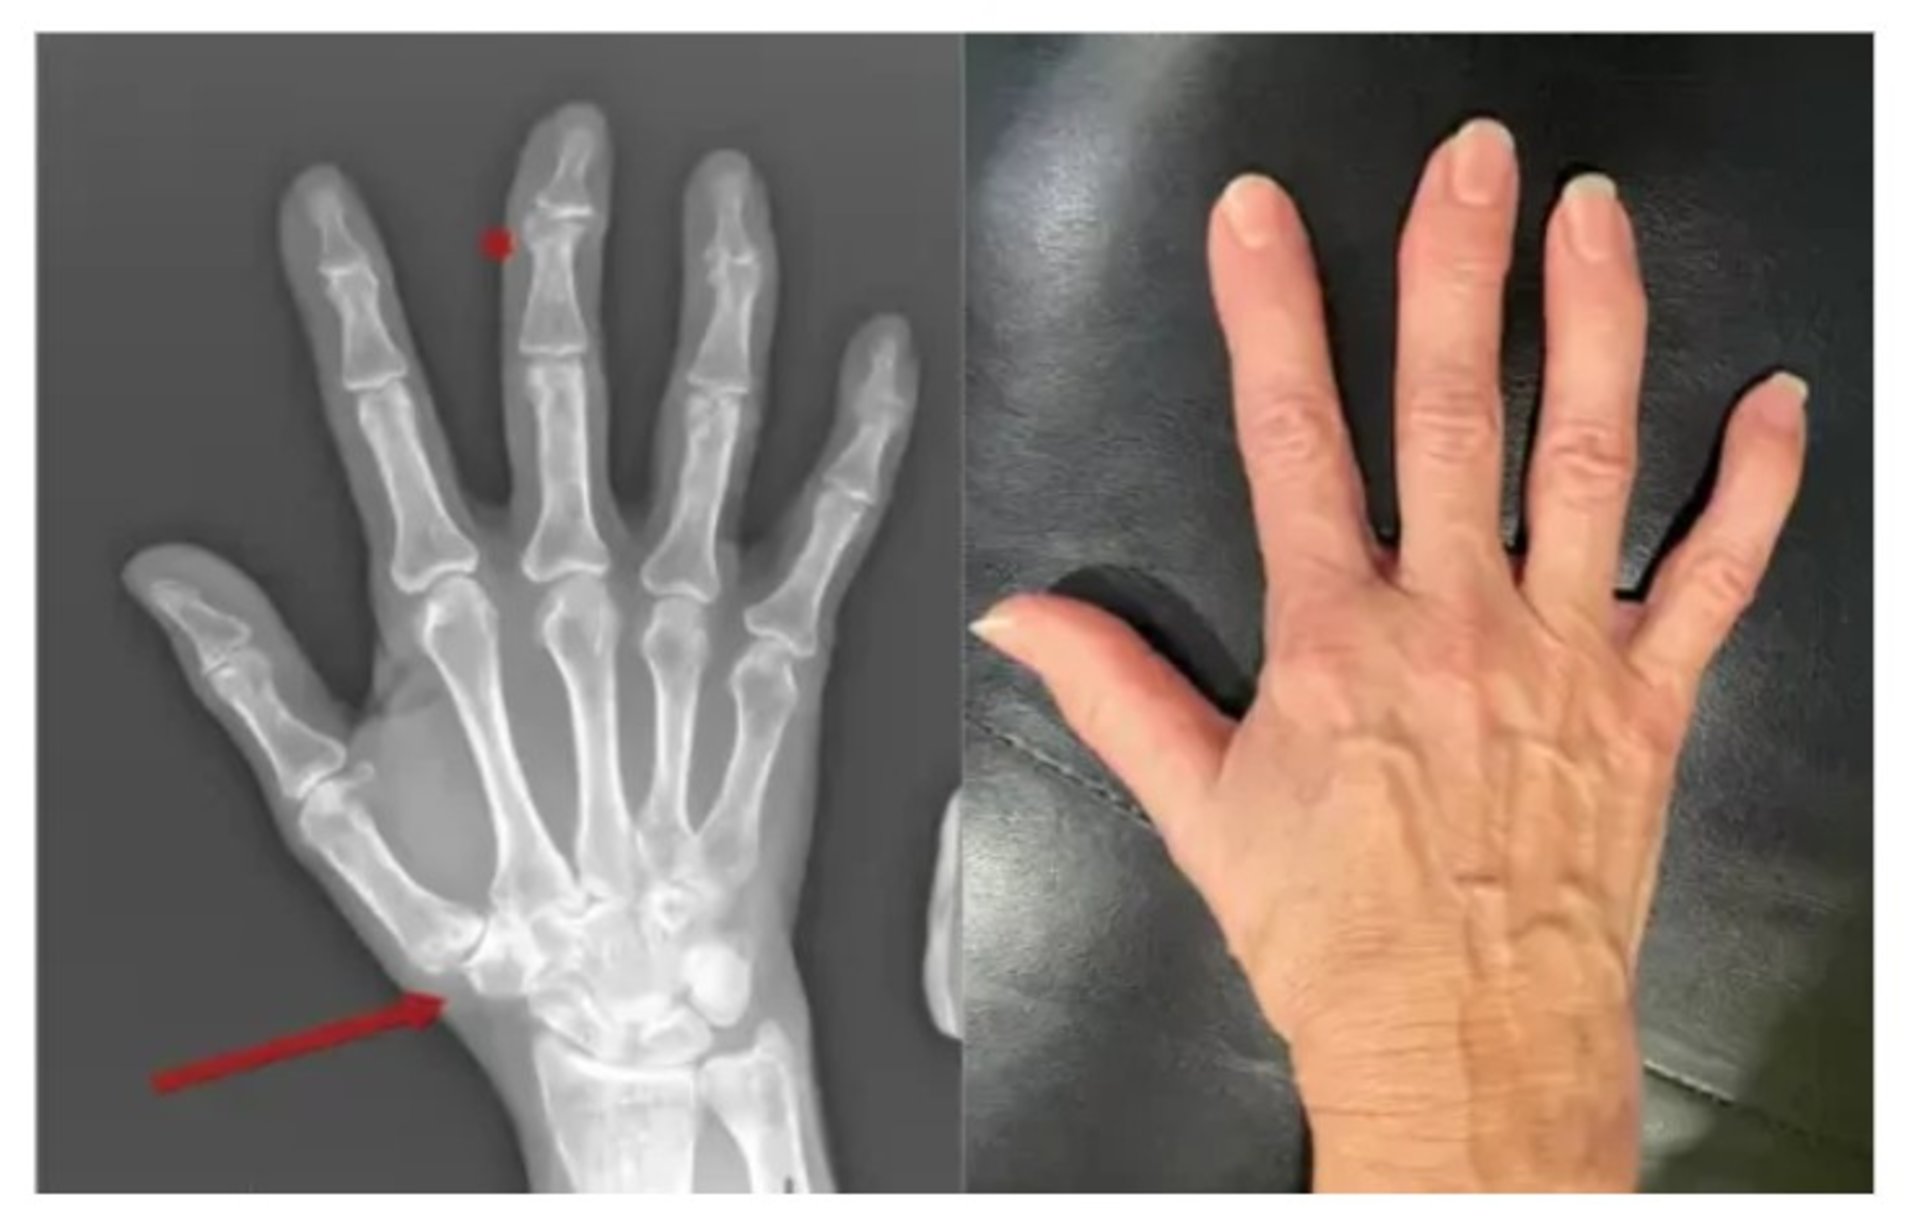

Остеоартроз розвивається поступово, і перші симптоми можуть бути майже непомітними – легка ранкова скутість, дискомфорт після фізичного навантаження або короткочасний біль у суглобах. З часом хрящова тканина втрачає еластичність, з’являється тертя, запалення й характерний «хрускіт», що заважає рухатися вільно. До ключових причин належать вікові зміни, надмірна вага, травми, спадкові фактори чи надмірні навантаження. Якщо процес прогресує, погіршується якість життя, зменшується обсяг рухів і зростає ризик деформацій.